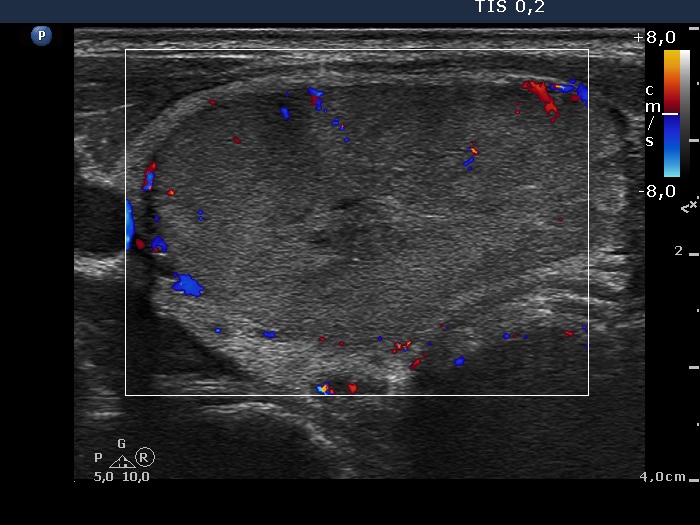

Ultrasonography. The thyroid was echonormal. There was a minimally-moderately hypoechogenic nodule in the right lobe. The presence of halo was doubtful, the lesion displayed perinodular blood flow.